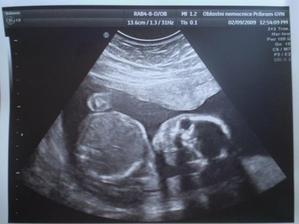

9.2. velký ultrazvuk máme za sebou, miminko je v pořádku 🙂, pohlaví nechceme znát, bude to překvapení

6.4. ultrazvuk kontrola dopadla dobře, miminko má cca 1230g, krásně si lebedí v bříšku a vypadalo moc spokojeně